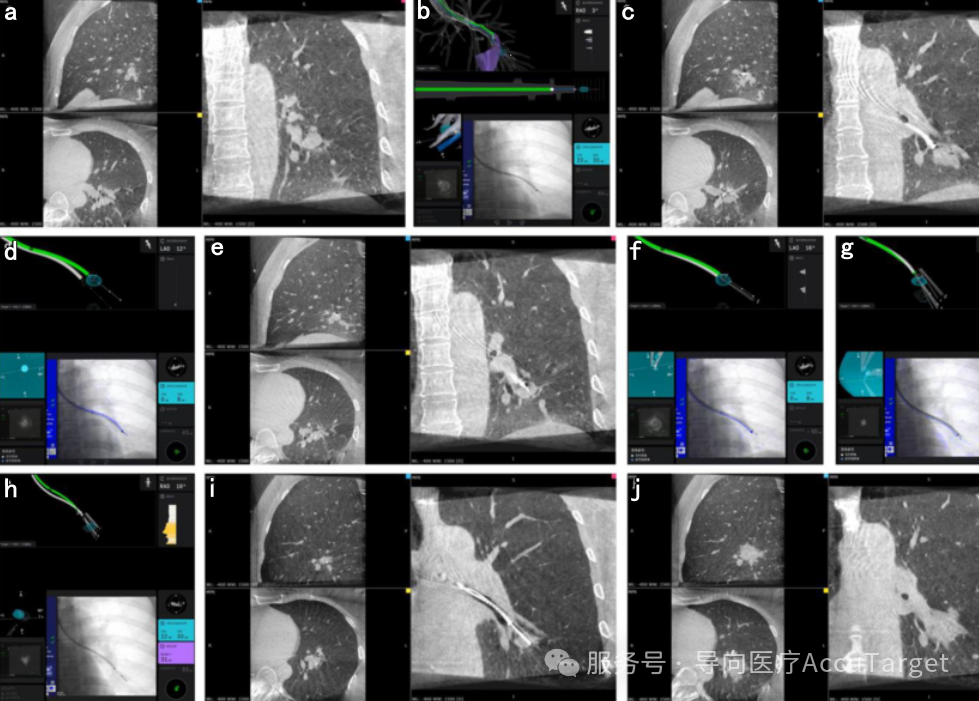

▲ 机器人+CBCT+红袖刀®

▲ 病例4-ssRAB联合CBCT引导下活检与冷冻消融。(a) 消融术前CBCT扫描;(b) 导航定位后,采用R-EBUS确认结节位置;(c) CBCT确认导管尖端与目标结节的位置关系;(d) 根据更新的结节位置进行穿刺;(e) CBCT确认穿刺针位于病灶内;(f) 经穿刺针建立隧道并使用针鞘扩张;(g) 钳夹行经支气管活检;(h) 置入冷冻消融探针并适当回撤导管;(i) CBCT确认探针位于病灶内;(j) 消融后即刻行CBCT扫描。